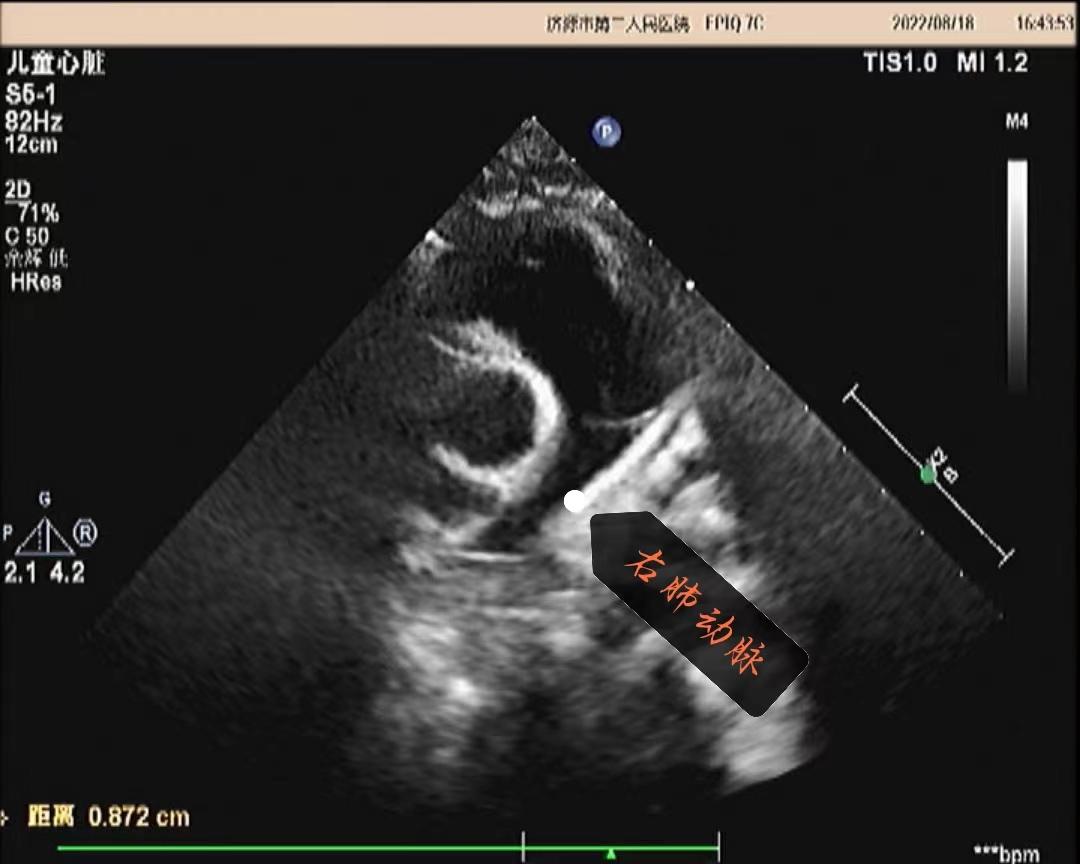

超声所见:各房室大小正常,肺动脉主干内径增宽,约20mm,左、右肺动脉内径分别约10mm、8.7mm,左、右肺动脉未见有狭窄,左肺动脉起始于主肺动脉的右侧并向左侧走行,右肺动脉起始于主肺动脉左侧向右走行。主动脉内径正常,搏动好。各瓣膜回声正常,肺动脉瓣开启可,关闭欠佳,余瓣膜启闭自如。房室间隔连续完整,室壁厚度及运动收缩幅度正常。CDFI:主肺动脉及左、右肺动脉前向流速增快。主肺动脉峰值流速:2.5m/s。左肺动脉峰值流速:2.2m/s。右肺动脉峰值流速:1.7m/s。肺动脉瓣口探及舒张期少量返流。

超声提示:1.左右肺动脉交叉 2.肺动脉主干内径增宽 3.肺动脉主干及左、右肺动脉前向流速增快 4.肺动脉瓣少量返流

(肺动脉主干及右肺动脉)